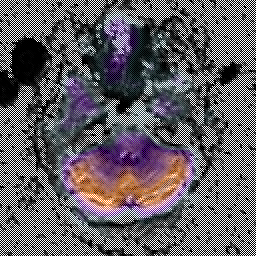

Alzheimer's Disease: SPECT/fMRI overlay -- Slice #1